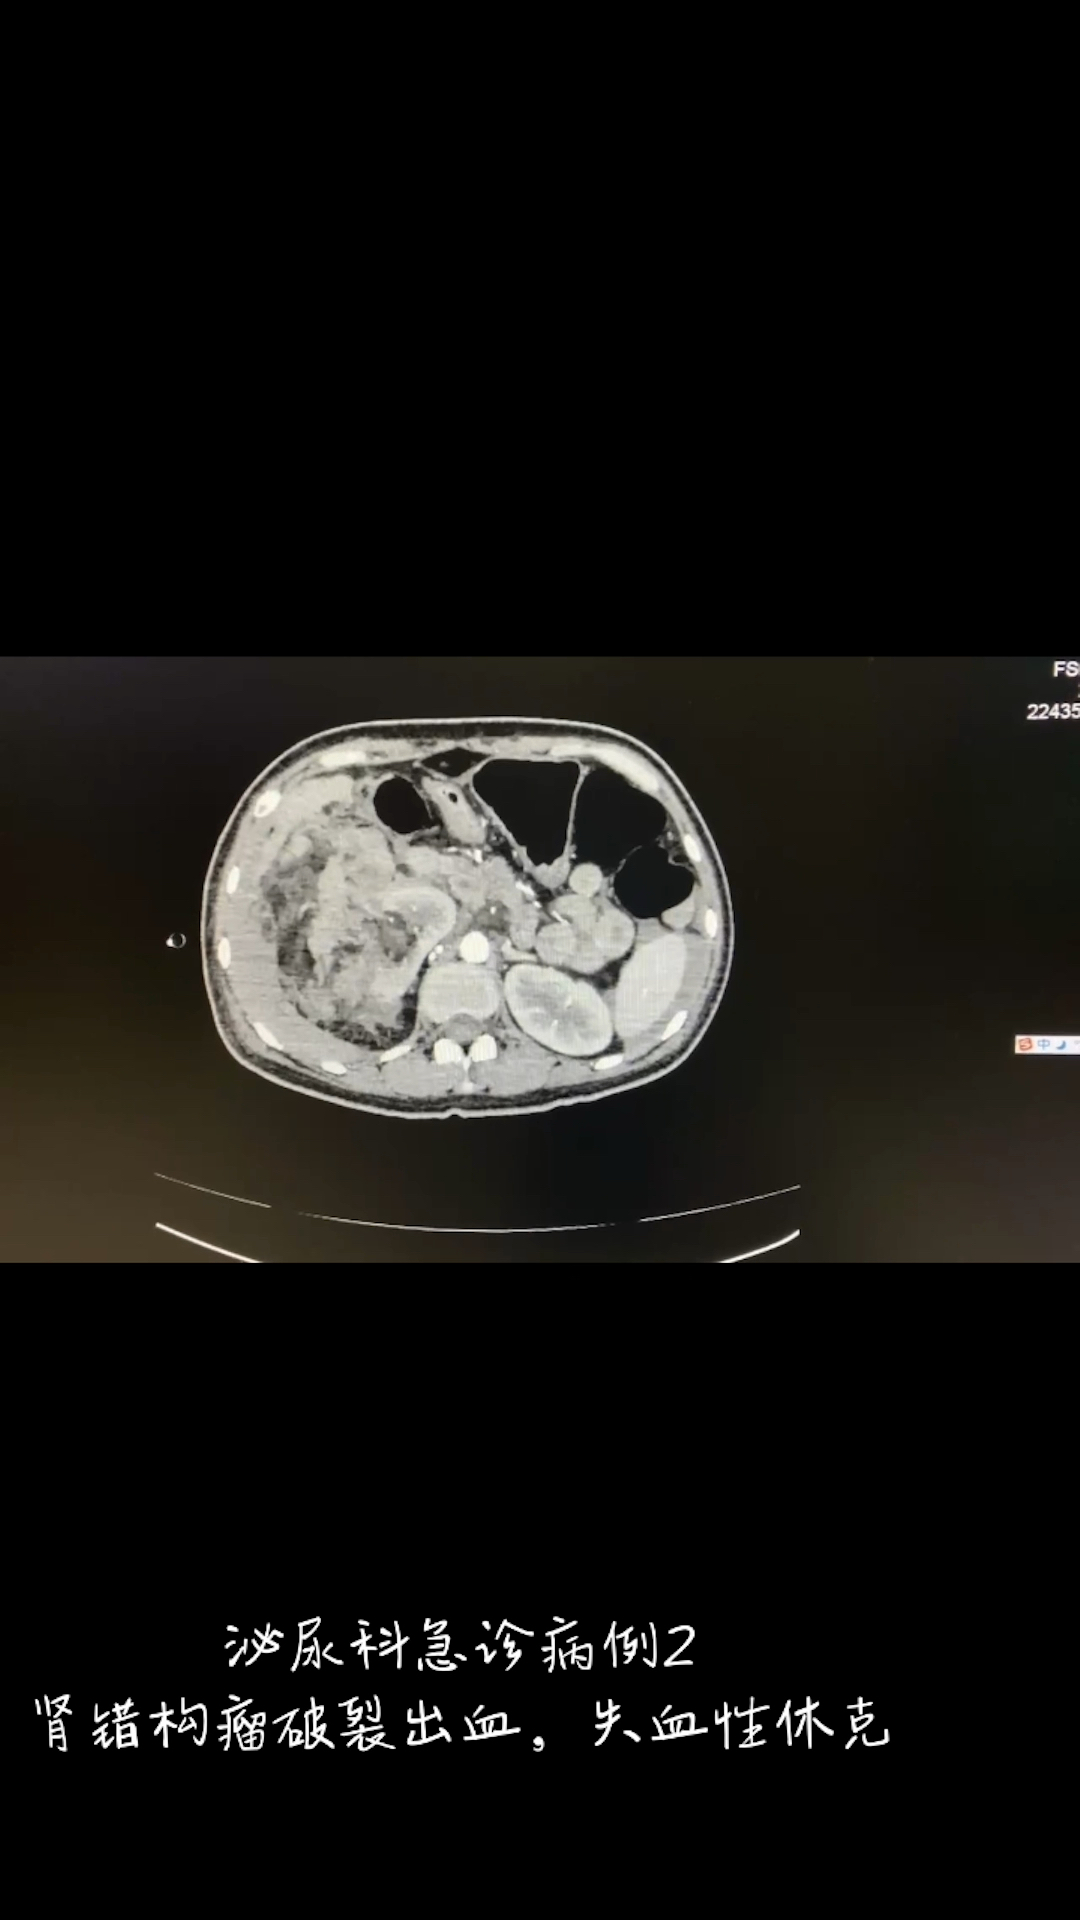

肾错构瘤破裂出血,失血性休克,抢救争分夺秒